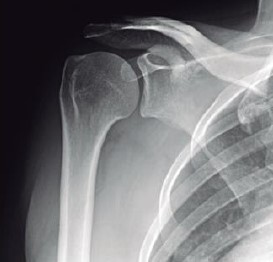

O exame de ombro, denominado de AP verdadeiro, é obtido com angulação do raio a 45° de medial para lateral, com o braço ao longo do corpo. Outra opção alternativa seria rodar o paciente até que a escápula fique encostada no filme e o raio incida perpendicularmente à escápula. Essa incidência tem como objetivo principal evidenciar a articulação glenoumeral e o espaço subacromial.

BONTRAGER,K. L; LAMPIGNANO, J. P. Manual prático de técnicas e posicionamento radiográfico. Rio de janeiro:Elsevier, 8 ed., 2014 (adaptado).

De acordo com a imagem é correto verificar que o posicionamento do paciente foi